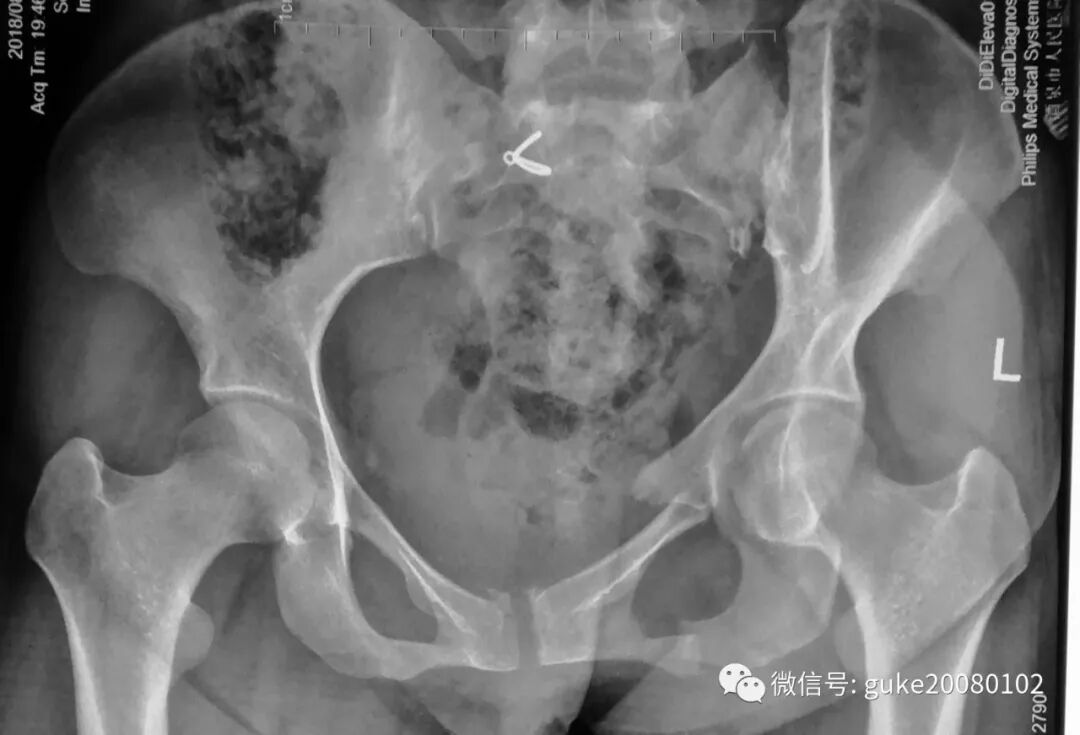

左耻骨骨折合并左骶髂关节分离 医联

左侧髂骨粉碎性骨折 右侧耻骨上下支骨折 涪陵桂林骨科医院

左髂骨及耻骨上下枝粉碎性骨折伴耻骨联合分离 影像资料 老年骨科网 老人自己的网站